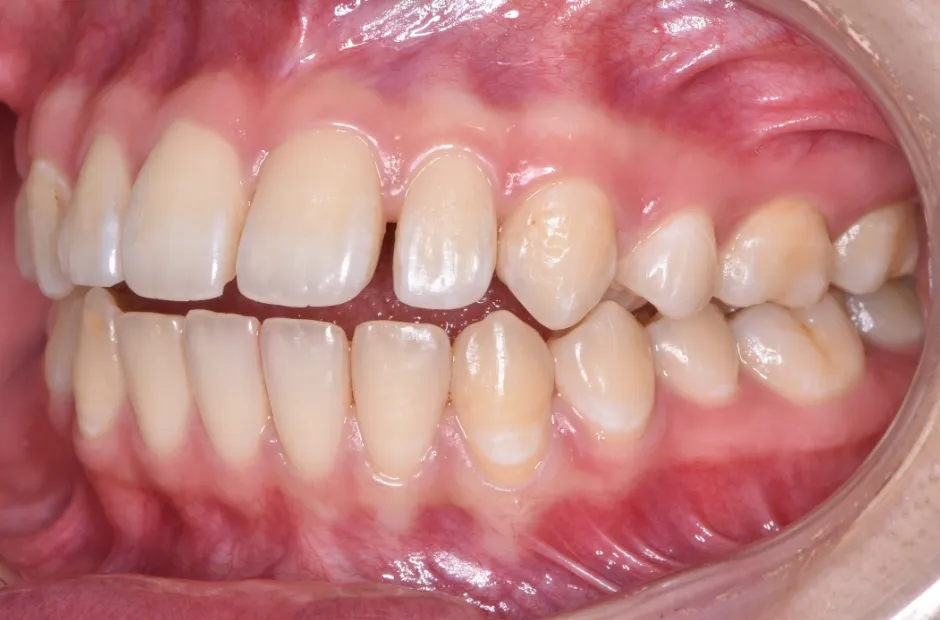

反対咬合

| 診断名・主訴 | 下顎前突、叢生 |

|---|---|

| 年齢・性別 | 23歳・女性 |

| 治療期間・回数 | 3年 |

| 治療に用いた主な装置 | 上顎5,5 下顎4,4 |

| 抜歯部位 | 舌側矯正 |

| 治療費 | 100万円(税抜) |

| リスク・副作用 | 装置による違和感・疼痛・歯肉退縮・歯根吸収・虫歯のリスクなど |

治療前

治療中

治療後